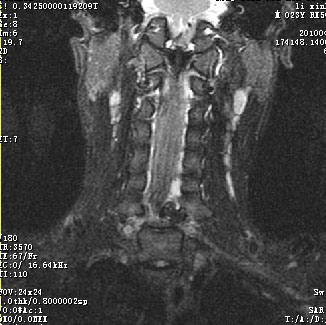

标题: 考虑骨软骨瘤可能性大

椎管内骨性肿块,与第7颈椎左下关节突关系密切,向椎管内生长,第7颈椎椎体左后缘受压变形,边缘可见硬化边,与肿块间间隙清晰。mri扫描肿块内可见骨髓信号,考虑骨软骨瘤可能性大。

考虑c7左侧椎弓根部骨软骨瘤。